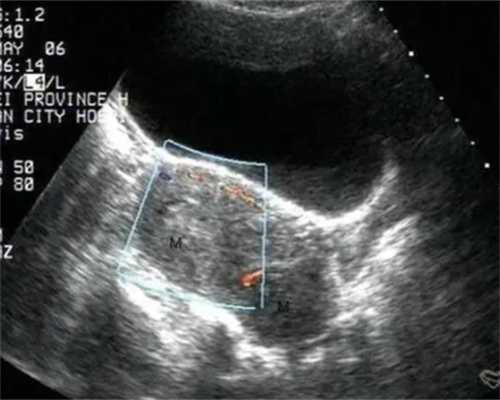

第三代试管婴儿技术(PGD/PGS)通过胚胎植入前遗传学检测,在特定条件下能够识别胚胎的性染色体组合,从而实现性别筛选。这项技术虽然主要用于筛查染色体异常和预防遗传病,但在严格的医疗指征下,对于部分家庭而言,这可以作为代生的一种辅助手段。了解代怀技术的进步,有助于规划家庭的未来。